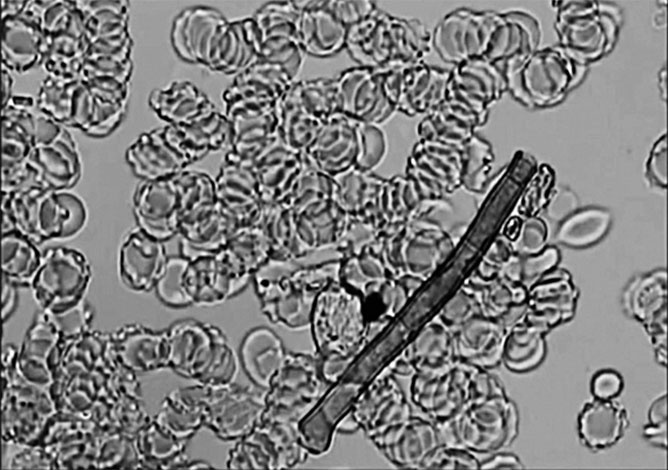

Лучше всего пояснять на конкретных примерах. Иллюстрации возьмем из атласа, по которому обучают операторов-новичков. Я раздобыл его на одном из семинаров по гемосканированию, где «под прикрытием» собирал материал для очередной статьи.

Паразиты

Любимый диагноз всех околомедицинских мошенников, и кудесники темнопольных микроскопов не исключение. Диагноз очень удобный: его сложно однозначно подтвердить или опровергнуть в силу особенностей физиологии паразитов и несовершенства традиционных методов их обнаружения. Поэтому разнообразных глистов и личинок псевдодиагносты находят практически у каждого пациента.

Иллюстрация к книге — Пациент Разумный. Ловушки "врачебной" диагностики, о которых должен знать каждый [i_006.jpg]

Яйца глистов

Действительно, в крови можно обнаружить яйца и подрастающие особи некоторых гельминтов. Например, у шистосом есть период гематогенной диссеминации (проще говоря, распространения по организму с током крови). Их яйца – овальные образования размером 104–203 на 50–85 мкм [57]. Диаметр капилляров в подушечке пальца, из которой берут каплю крови для гемосканирования, – около 5 мкм. Внимание, вопрос: как яйца паразитических червей туда втиснутся? Как проходят эритроциты, диаметр которых около 7,5 мкм, известно: они обладают эластичной мембраной, которая может до определенной степени деформироваться, вытягиваться. После этого красные кровяные клетки способны преодолеть капилляр дружным строем, по одному, друг за другом. И что делать гигантскому, в десять раз больше эритроцита, яйцу или еще более крупной личинке? А ничего. Довольствоваться крупными сосудами. Вот в венозной крови их как раз и можно чисто теоретически обнаружить, если застать нужный момент. Еще в кровоток умеют выходить аскариды, но размер их оплодотворенных яиц – 45–75 на 35–50 мкм [58], а подрастающие и взрослые особи существенно крупнее.